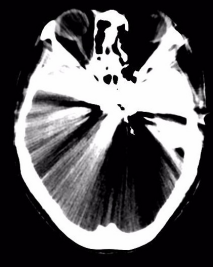

附女士,今年50岁,因车祸头部受伤,意识障碍4小时急诊入院。入院时,患者呈昏迷状,左侧瞳孔散大,头部、腕部、腹部等受伤10余处。急诊CT提示硬膜外血肿,中线移位明显,脑实质明显受压内移,左侧侧脑室受压变窄,病情凶险,手术指征明确。

(术后血肿清除彻底)

术后第一天,患者意识恢复清醒,复查头部CT提示颅内血肿清除彻底。全腹CT、双腕关节CT显示:肠管管壁明显水肿增厚,邻近肠系膜肿胀,肠间隙模糊,盆腔少量积液,腹腔内未见游离积气,提示肠管或肠系膜损伤;右侧月骨脱位,左侧桡骨远端骨折。